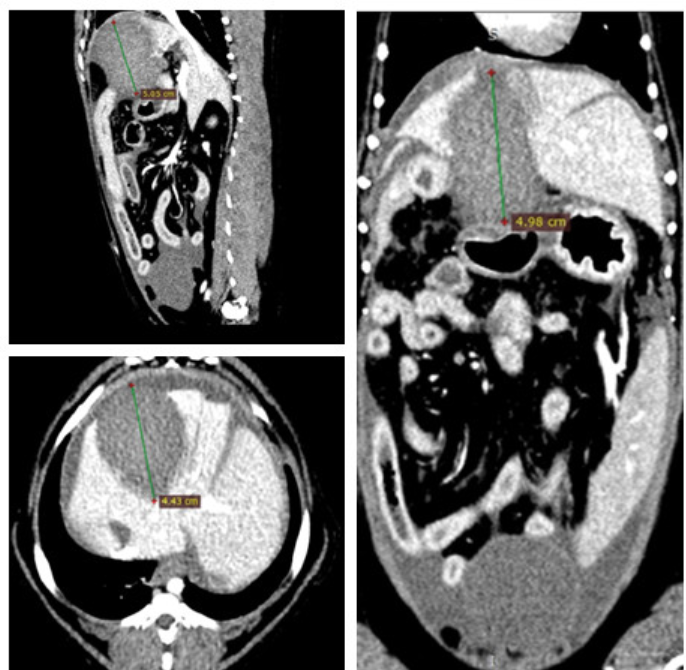

临床诊断发现它坐卧不安,呼吸沉重,伴随恶心的症状。随后B超发现了3-5公分回声不均的团块,为了判断这个团块,院长又给卡卡安排了进一步检查——CT扫描。

通过CT结果,确诊卡卡是患了胆囊黏液肿,如果穿孔则会引起腹膜炎,生命危在旦夕;根据目前的患病情况,院长给卡卡制定了最有效的的治疗方案——胆囊切除手术!